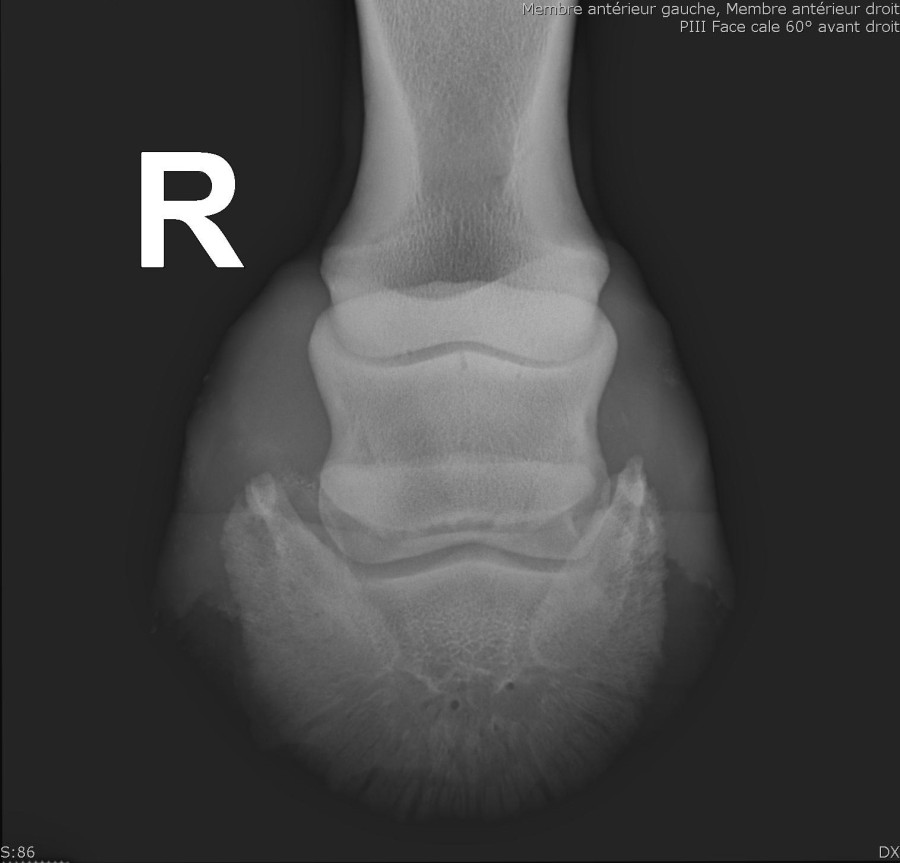

Je viens de réaliser une visite d'achat sur une jeune jument de 3 ans, non débourrée, qui présente sur chaque antérieur une "fossette synoviale au bord du distal naviculaire".

Le véto ne semble pas plus inquiet que ça mais a quand même émis un avis "suspect" sur les radios.

Je vous joins les photos